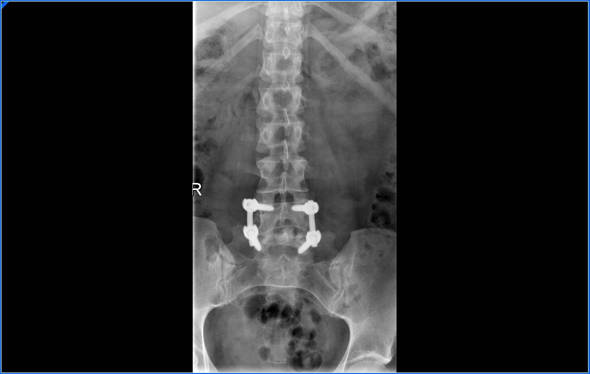

Todo empezó con 33 años, esté he cumplido 40, mi primera cirugía fue para solucionar una hernia discal, 5 meses después tenía una recidiva de la hernia, tenía que volver a pasar por quirófano y esta vez me iban a poner tornillos y fusionar dos vértebras.

Pero el dolor continuaba y había que entrar de nuevo en quirófano, esta vez eran las articulaciones sacroilíacas, teníamos que fusionarlas, una técnica poco invasiva pero a su vez era una técnica nueva que estaban empezando hacer así que decidimos emprender de nuevo el camino.

La primera artrodesis sacroilíaca la llevé más o menos bien, era la parte derecha, las fijaron con 3 tornillos de titanio y la cosa no es que hubiese mejorado mucho, así que teníamos que hacer la parte izquierda y esa sí que fue dura de verdad, mi pierna izquierda no es la más fuerte, es la del pié equino y siempre me había dado muchos problemas, musculatura atrofiada, psoas, isquiotibial, piramidal, esos músculos que parecen sacados de un partido de fútbol estaban dando demasiada guerra y desesperación por todas partes. Que más se podía hacer?; Si ,hay que fijar la vértebra que queda suelta pero…necesito estar 100% en todo para poder pasar por ahí, no solo físicamente sino moralmente.